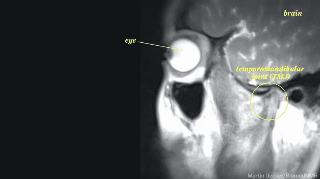

Si alguna vez te preguntaste cómo se verían desde nuestro interior algunas de las prácticas que todos los humanos realizamos, hoy te lo muestro. Gracias a las resonancias magnéticas, se puede ver el interior de nuestro cuerpo a la perfección.

3. El ojo mientras miramos.